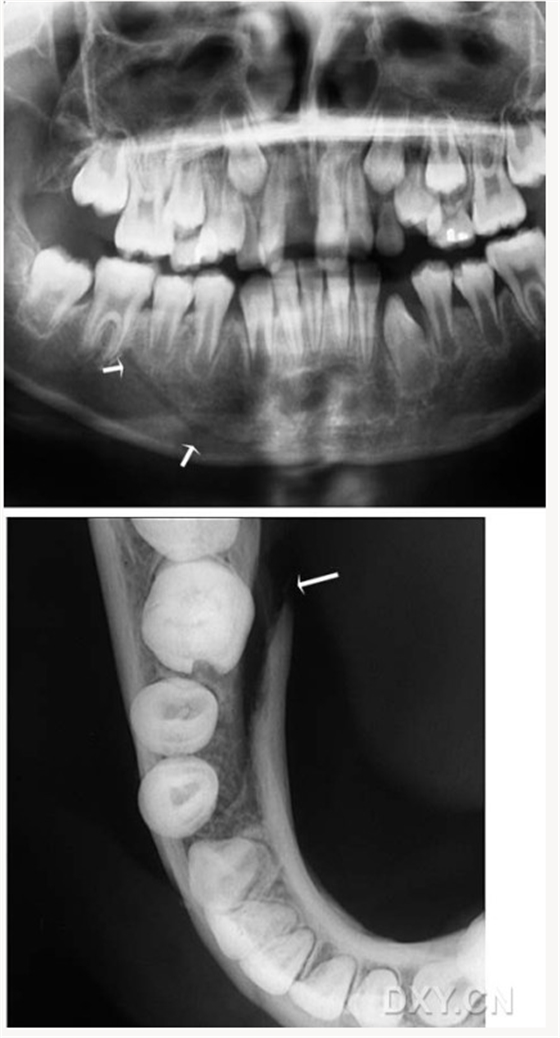

良性成牙骨質(zhì)細(xì)胞瘤